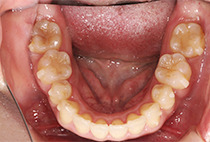

出っ歯と前歯のガタつきにお悩みだった20代女性の症例です。

前歯のガタガタ、中心のずれ、顎のずれ、外科矯正は避けたい

叢生、左右非対称咬合

矯正治療2年6ヶ月